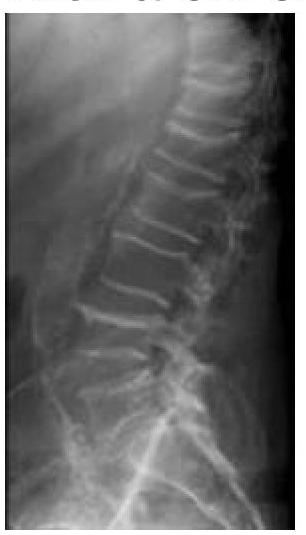

What is the diagnosis of a 55-year-old woman with chronic low backache?

Explanation: ***Osteoporosis*** - The image shows **loss of bone density** and **vertebral compression fractures**, especially visible in the lumbar spine, which are characteristic findings in osteoporosis. - Osteoporosis is common in post-menopausal women, and **chronic low backache** is a frequent symptom due to microfractures or vertebral collapse. *Hurler's syndrome* - This is a lysosomal storage disease (mucopolysaccharidosis type I) that primarily affects **children** and presents with distinct **skeletal deformities** (dysostosis multiplex), facial features, and organ involvement. - It would not typically present as chronic low backache in a 55-year-old woman, and the radiological findings are not consistent with Hurler's syndrome. *Paget’s disease* - Paget's disease of bone involves abnormal bone remodeling, leading to **enlarged and weakened bones**, often with a characteristic **cotton wool appearance** on X-ray, which is not seen here. - While it can cause bone pain and affect the spine, the primary radiological features seen in this image are more consistent with generalized bone density loss and fractures rather than focal expansion and abnormal bone architecture. *Renal osteodystrophy* - This condition occurs in patients with **chronic kidney disease** and results from imbalances in calcium, phosphate, and parathyroid hormone. - Radiographic features include **osteosclerosis (rugger jersey spine)**, bone erosions, or osteomalacia, which are different from the generalized osteopenia and compression fractures observed in this X-ray.